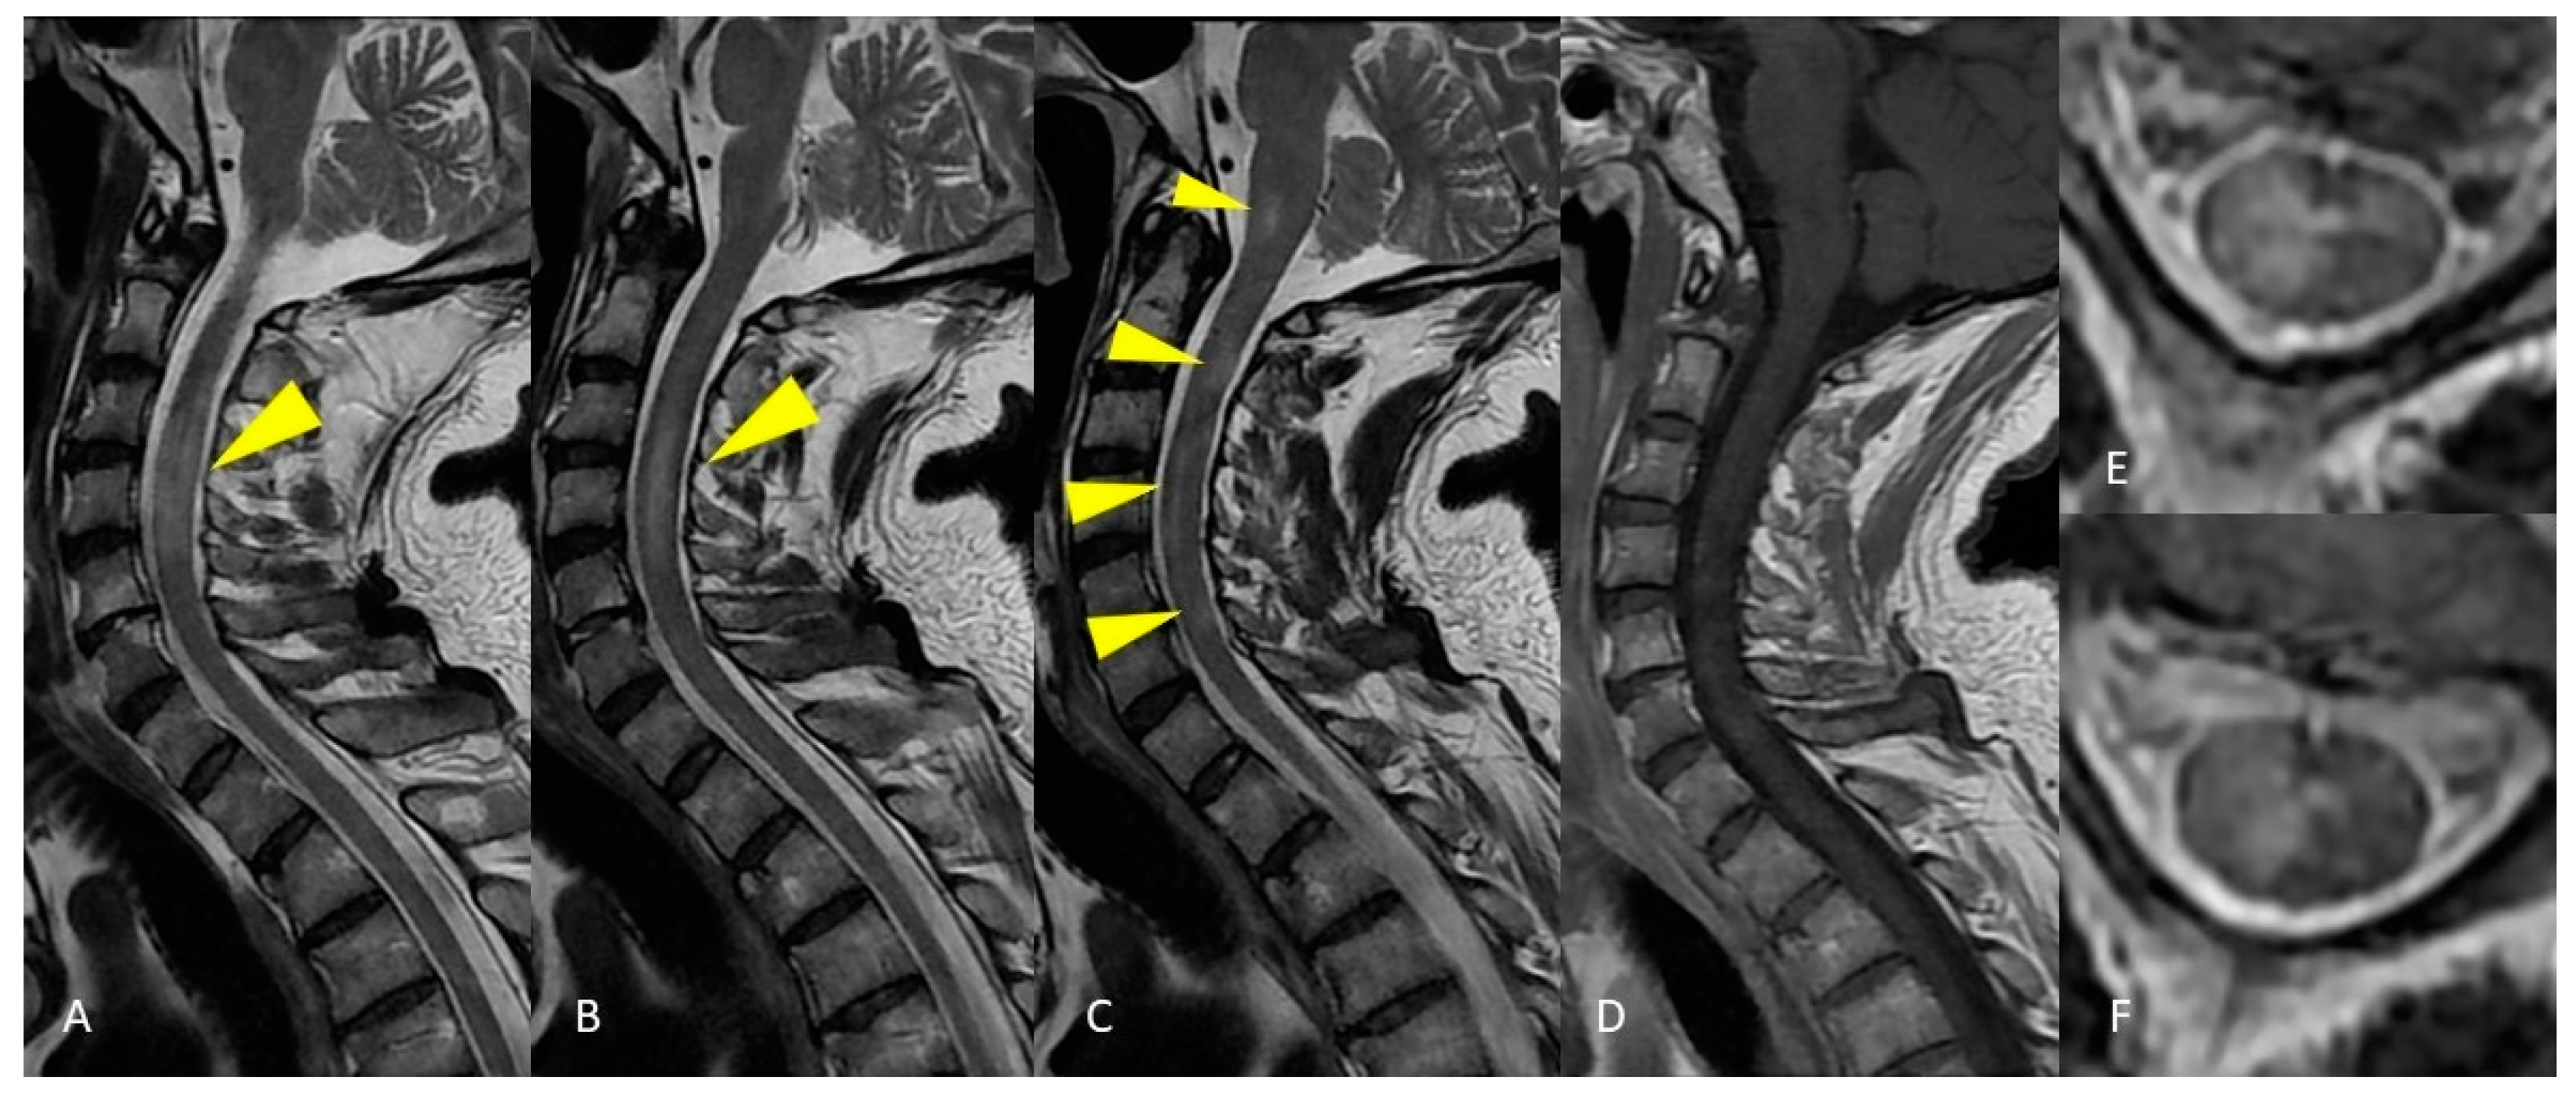

2.1. Case Presentation 1

2.2. Case Presentation 2

3.3. Neuromyelitis Optica—NMO